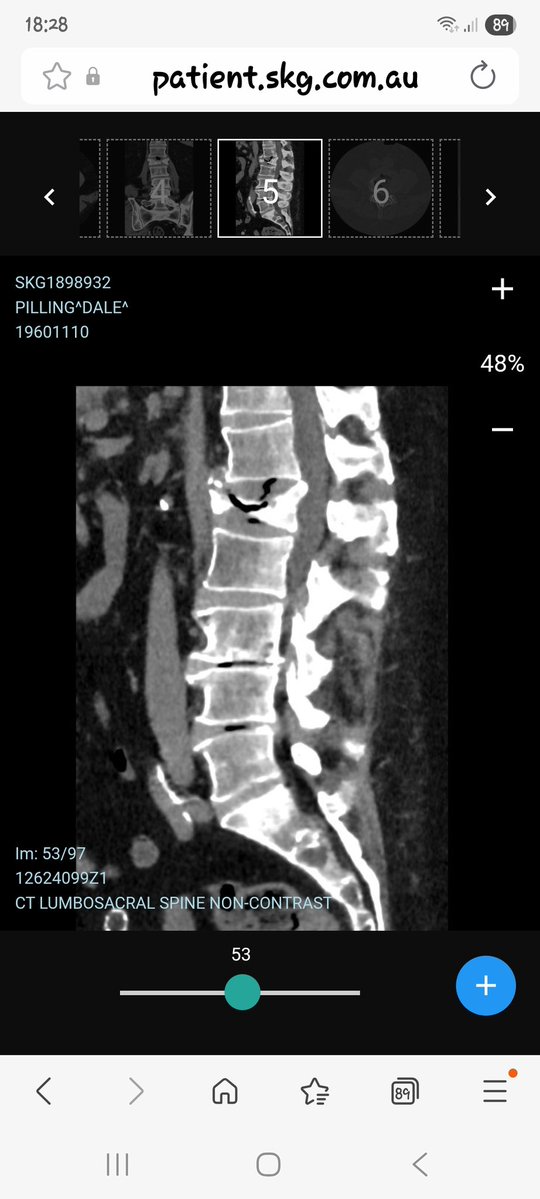

Thanks mate, the scan went well but spine is still stuffed.

Freo_Dale's tweet image. Thanks mate, the scan went well but spine is still stuffed.